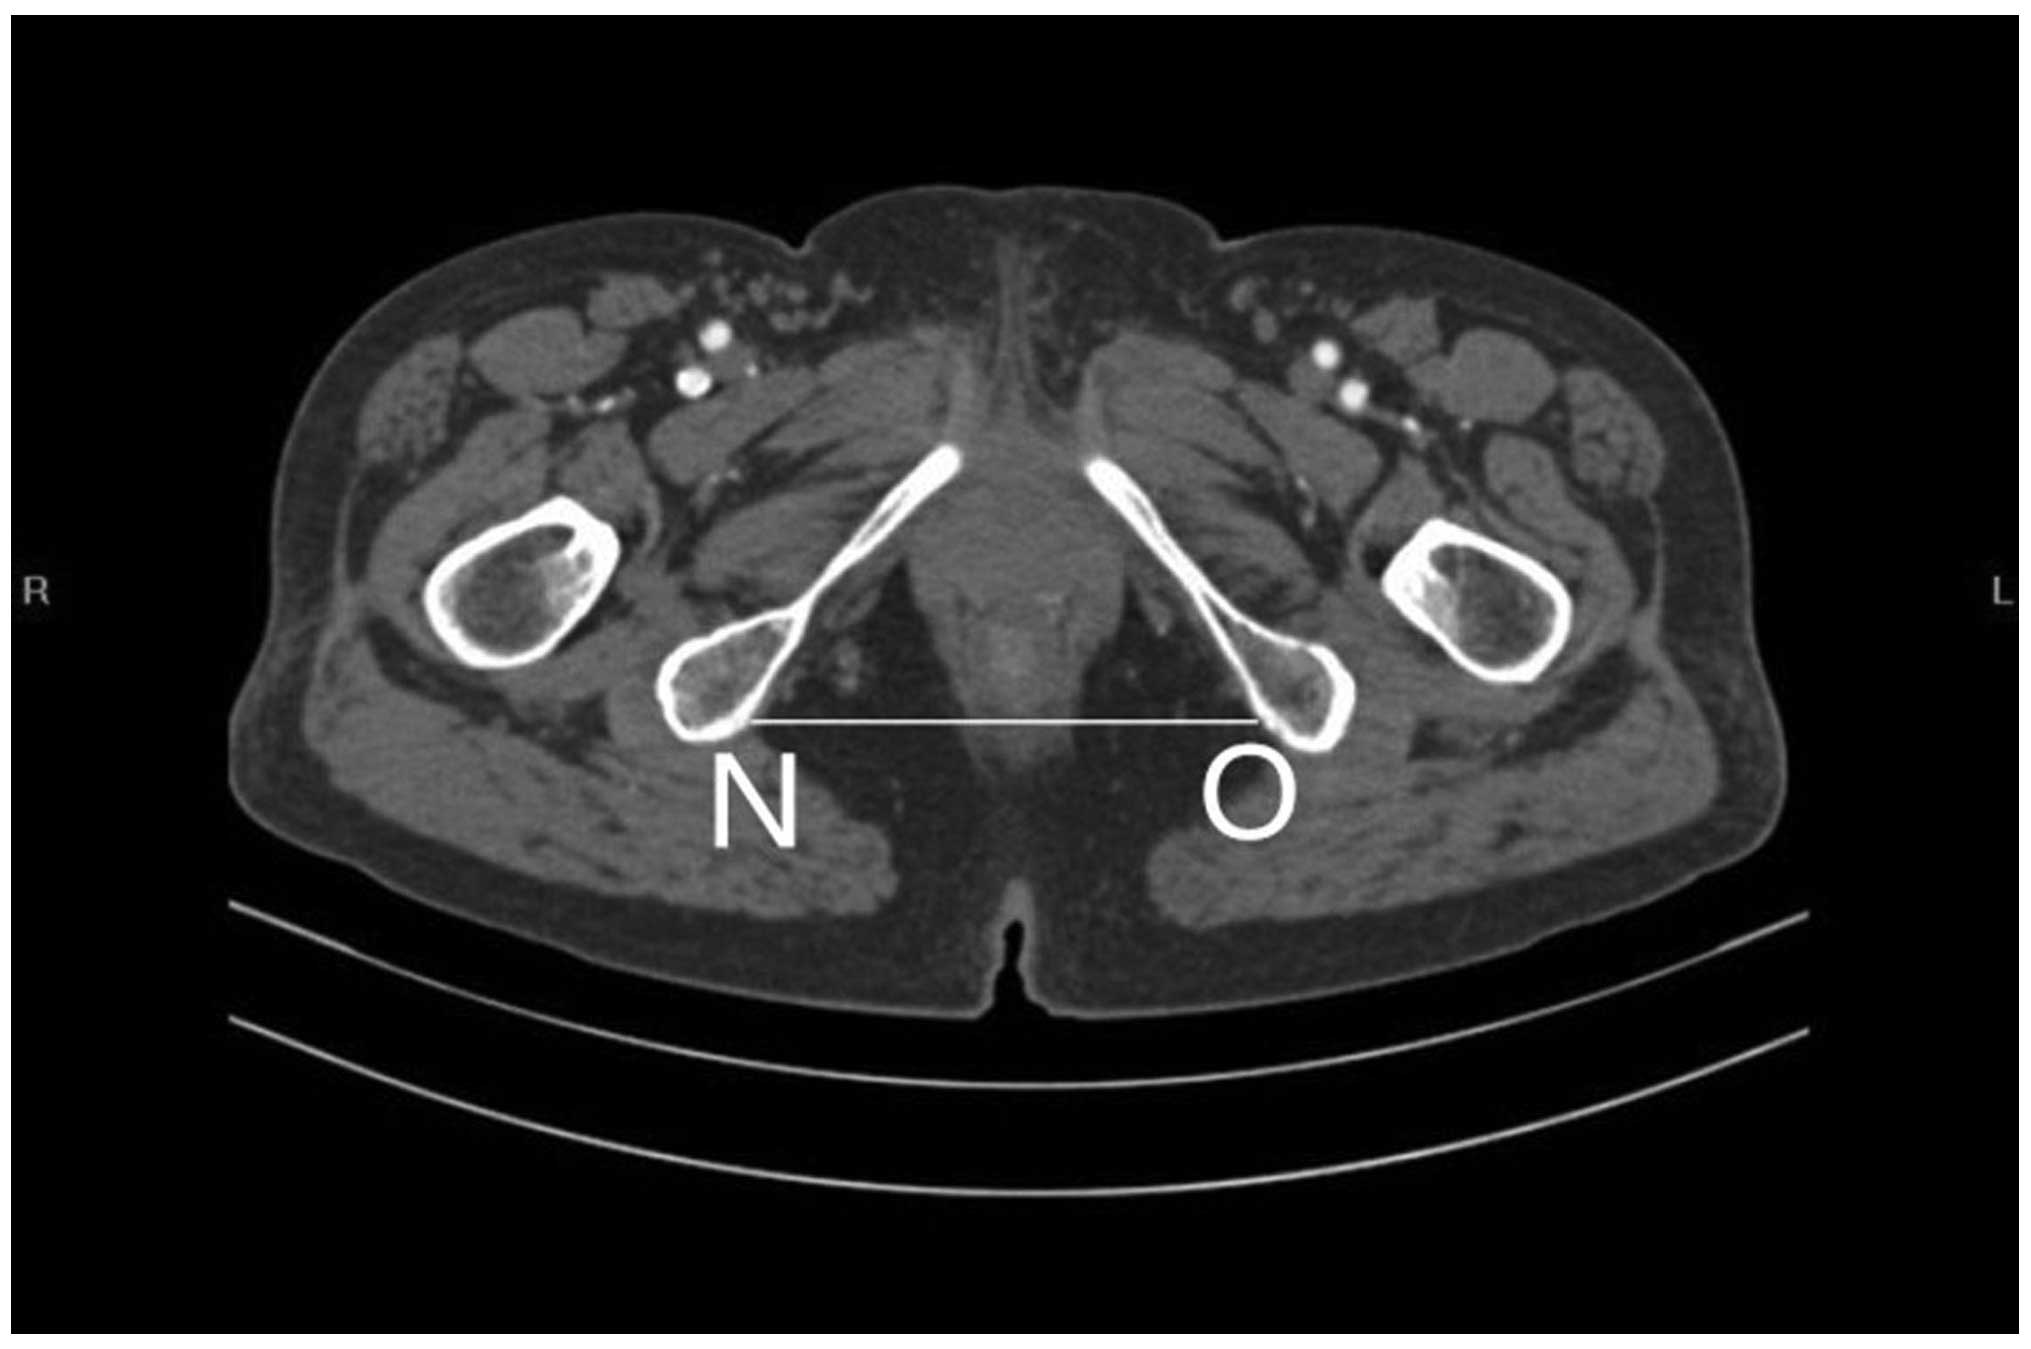

5. The intertuberous diameter (NO).

Figs. 1 and 2 outline the mid-sagittal view of the pelvis in a female patient. Fig. 3 outlines the axial section, showing the interspinous diameter of the mid-pelvis. Fig. 4 outlines the axial section, showing the intertuberous diameter of the pelvic outlet. The relevant measurements are indicated in Figs. 1–4. Assessment of intraobserver error was conducted as detailed in the statistics section.

Figure 4.

Axial section showing the intertuberous diameter (NO) of the pelvic outlet.